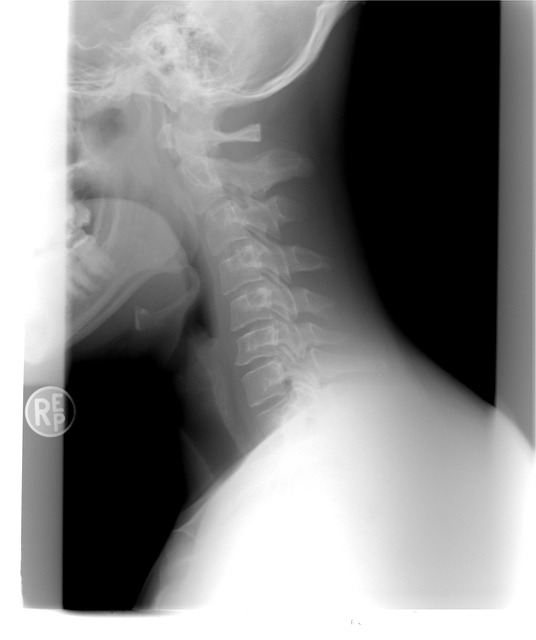

주변을 둘러보면 갑상선에 대한 질병을 흔하게들 많이 들어보셨거나 볼 수 있으실거에요. 갑상선은 우리 목에 위치해 있는데요. 신진대사에 필요한 갑상선 호르몬을 분비하는 내분비기관을 말합니다.

갑상선 목부음은 갑상선종으로 불리우는데요. 이게 크기가 커지거나 통증이 심해지면 숨을 쉬거나 음식을 삼키는데 불편함이 생겨 일상생활속에서 많은 불편함을 느낄 수 있다고 해요.